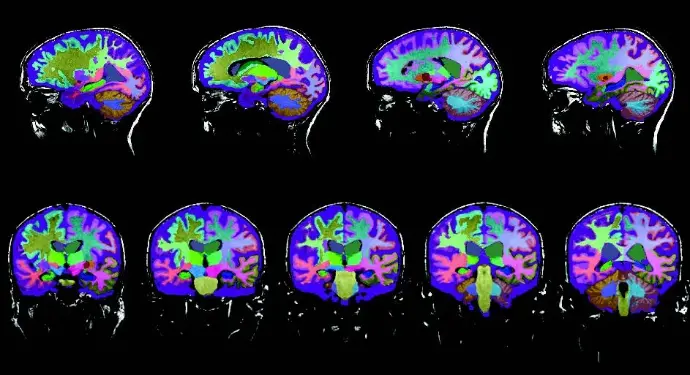

Neuroreader® has been independently validated in peer-reviewed research and clinical practice as a reliable, FDA-cleared tool for fast and accurate brain volumetric analysis. Dr. Cyrus A. Raji demonstrates how to interpret Neuroreader® Reports in the following clinical case studies:

A 78-year-old woman presented with progressive memory loss. To support clinical evaluation, her physician ordered a 3D T1 volumetric MRI sequence, which was analyzed using Neuroreader®, an advanced software for automated brain volumetry. The Neuroreader® Report provided objective, quantitative insights into her brain structure volumes, helping guide a more accurate diagnosis of Alzheimer’s dementia.

A 69-year-old woman with memory loss and depression underwent four MRI scans over seven years (ages 62, 64, 66, and 69). Using Neuroreader® volumetric software, progressive changes were quantified and tracked across key brain regions.

This case study highlights how automated MRI brain volumetrics can support the differentiation of frontotemporal dementia (FTD) from Alzheimer’s disease (AD) by objectively quantifying regional brain atrophy.

The patient is a 66-year-old man presenting with a gradual onset of personality changes and memory loss, a clinical profile that raises concern for a neurodegenerative process and often overlaps between FTD and Alzheimer’s disease.